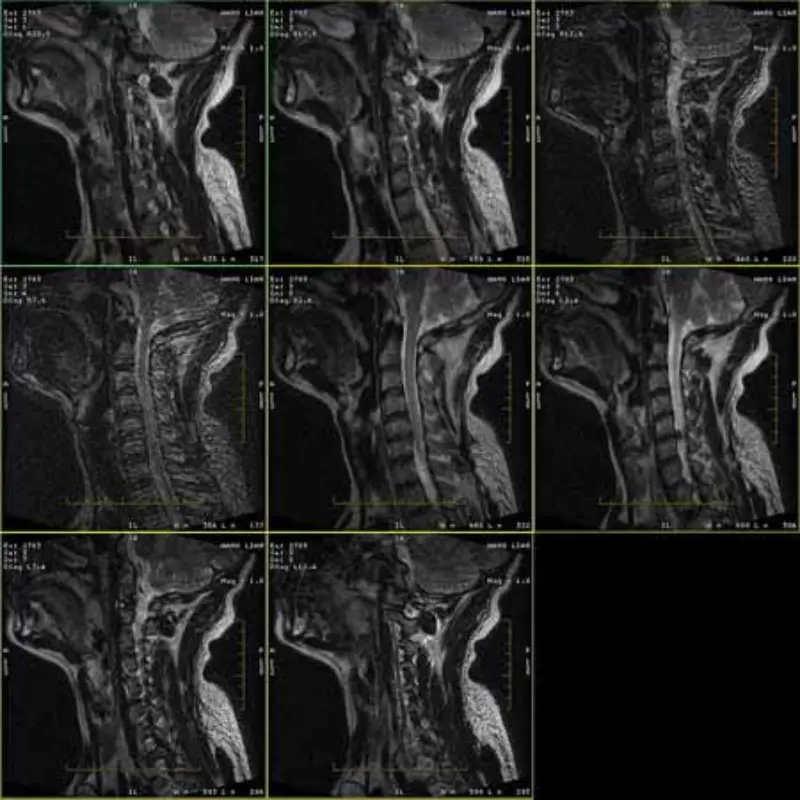

تصاویر پروتکل های FRFSE و GRE دارای شبح و گاهی اوقات تصاویر SNR کم در یک سری ظاهر می شوند. اما تصاویر پروتکل SE طبیعی هستند.

لطفا به تصاویر پیوست نگاه کنید